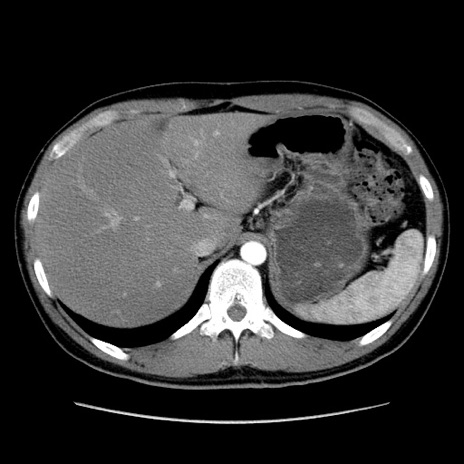

症例36(横断像)

【症例】20歳代 男性

【主訴】心窩部痛

【現病歴】今朝より上腹部痛あり。一旦軽快していたが再度出現したため救急要請。昨日夕に白身の魚を含む刺身を食べた。

【身体所見】BP 136/89mmHg、HR 74/min、BT 37.0℃、腹部:膨満、軟、心窩部に圧痛あり。反跳痛なし、筋性防御なし、腸雑音やや亢進あり。

【データ】WBC 17700、CRP 0.48